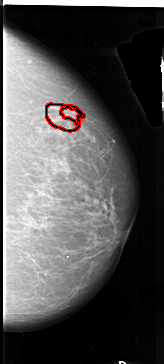

A_1012_1.RIGHT_MLO

RIGHT_MLO LINES 6781 PIXELS_PER_LINE 2821 BITS_PER_PIXEL 16 RESOLUTION 42 OVERLAY

FILE: A_1012_1.RIGHT_MLO.OVERLAY

TOTAL_ABNORMALITIES 1

ABNORMALITY 1

LESION_TYPE MASS SHAPE IRREGULAR MARGINS SPICULATED

ASSESSMENT 4

SUBTLETY 2

PATHOLOGY MALIGNANT

TOTAL_OUTLINES 2

BOUNDARY

CORE